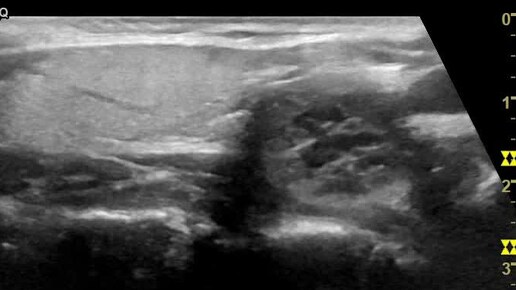

Видео к статье "Стратификация узлов щитовидной железы. TI-RADS-2"Адрес: https://dzen.ru/a/ZuUZLzUfMV_UqGyz